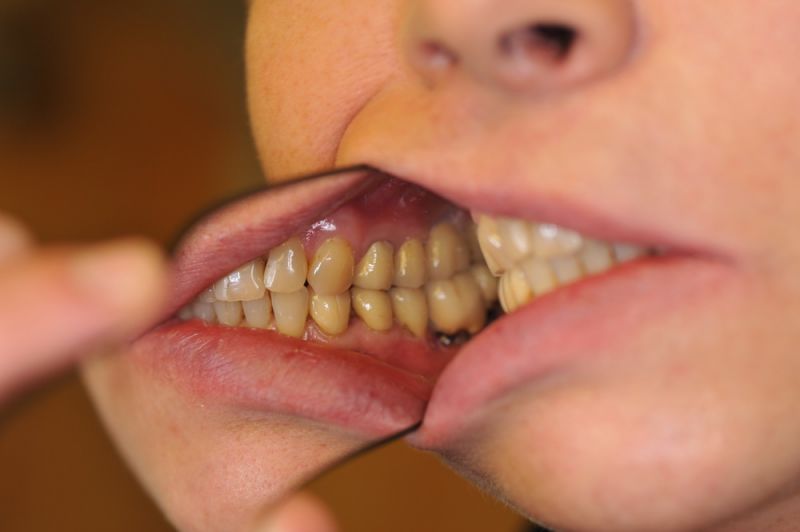

Schwierigster Fall aller Zeiten, praktisch beschwerdefrei. Patientin glücklich!

Der Fall einer Patientin aus Hamburg ist zwar bei weitem nicht der umfangreichste, oder gar teuerste Fall aller Zeiten, aber der Fall, der bei dem überschaubaren Umfang, das meiste Kopfzerbrechen bereitet hat und man darf es sagen, am Ende primär als sportliche Herausforderung gesehen wurde, ob man das überhaupt noch hinbekommt.

Und wir haben es hinbekommen! Die Patientin hat heute zum Ausdruck gebracht, dass sie das selbst nicht für möglich gehalten hätte.

Es war eine Kombination aus Schmerzen bis an die Suizidgrenze, beschränkten wirtschaftlichen Möglichkeiten, sehr stark eingeschränkten Möglichkeiten der für Implantate zur Verfügung stehenden Knochenverhältnisse in einem stark atrophierten Unterkieferseitenzahnbereich und zudem dann auch noch durch auftretenden Problemen bei der Implantatinsertion und nachfolgenden Versorgung der Implantate.